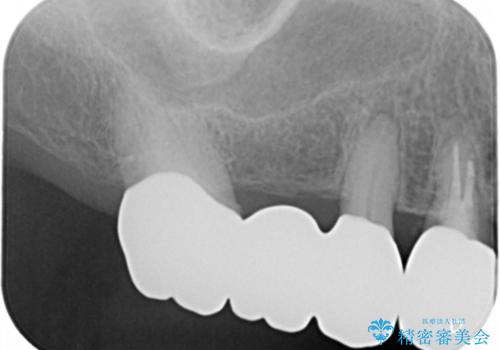

- 数十年前、アメリカで行った治療部位のやり直しを希望されてご来院。

ツギハギの修復が行われてきた被せ物は、縁が合っておらず隙間があり見た目も悪くなってしまっていました。

古い被せ物を除去し、中の状態をキレイにしたうえで改めて金属を使用していない被せ物で噛み合わせの回復を行いました。

被せ物の色は噛み合う反対側の被せ物と合わせて作りました。